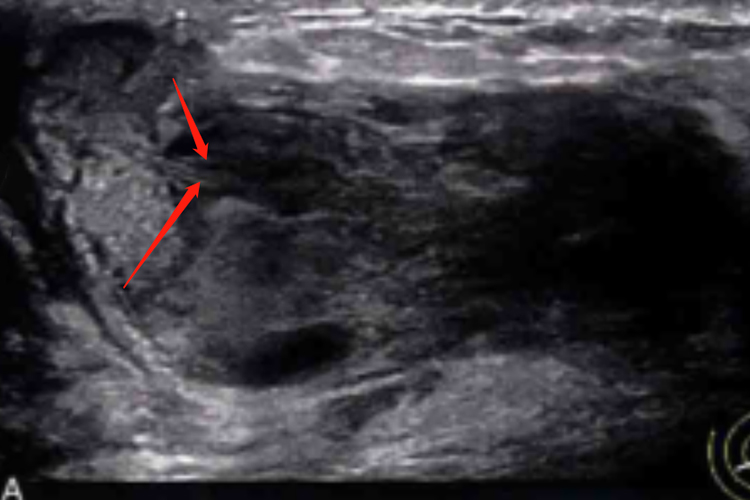

Ⅱ型:腺体层内出现沿乳管走行方向不均匀性的低回声团块,不均匀性低回声位于导管内和/或导管周围。